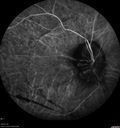

FLUORESCEIN ANGIOGRAPHY: Fluorescein angiography in the right eye shows leakage from the area of retinal infiltrate. In the left eye there is hypo and hyper auto fluorescence corresponding to the leopard spots.

INDOCYANINE GREEN ANGIOGRAPHY: The indocyanine green angiogram similarly shows the leopard spots in the left eye and leakage from the lesion in the right eye.

He has been on 20 mg of prednisone orally. His right eye now has fallen to no light perception. The left eye has some hazy vision. You were concerned about several things; one is mainly what possibilities there might be for diagnosis and therapy, especially to protect the left eye.

VISUAL ACUITY: OD: NLP, OS 20/50. IOP: 13 OU. The right eye has some crystal cellular growth within the LASIK flap and the ReSTOR intraocular lens is in good position. The left eye has a ReSTOR intraocular lens in good position.